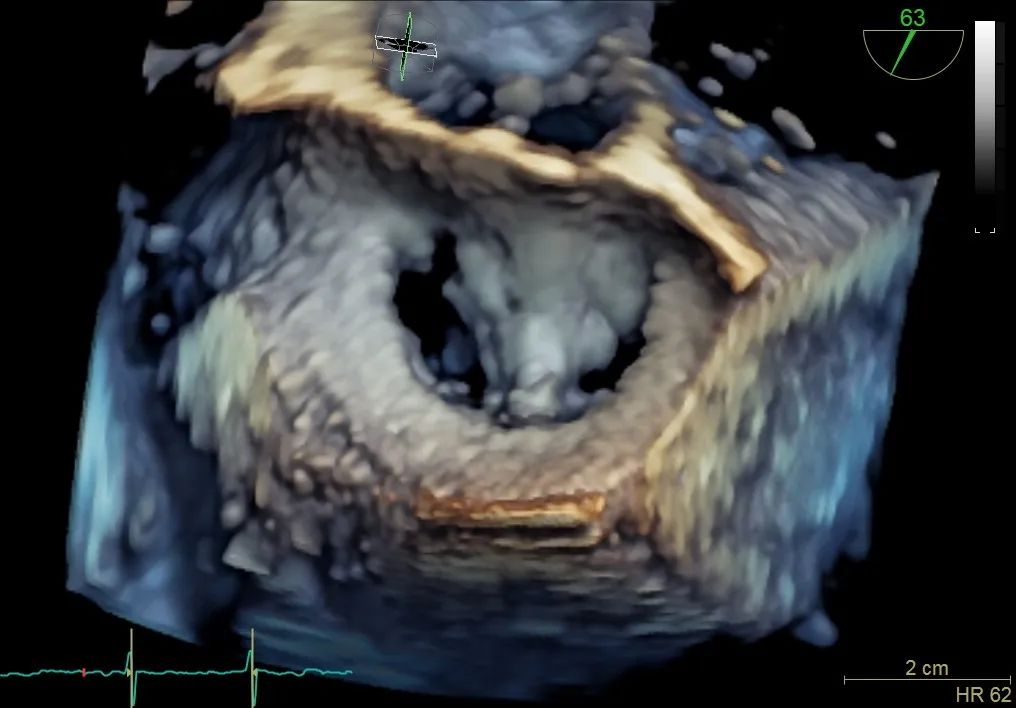

二尖瓣在收缩期变成双孔状,反流有效减小

再次反复测试第二枚二尖瓣钳夹的稳定性,超声复查提示二尖瓣反流明显改善,平均跨瓣压差4 mmHg